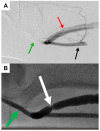

Dialysis associated steal syndrome (DASS) is a relatively rare but debilitating complication of arteriovenous fistulas. While mild symptoms can be observed, if severe symptoms are left untreated, DASS can result in ulcerations and limb threatening ischemia. High-flow with resultant heart failure is another documented complication following dialysis access procedures. Historically, open surgical procedures have been the mainstay of therapy for both DASS as well as high-flow. These procedures included ligation, open surgical banding, distal revascularization-interval ligation, revascularization using distal inflow, and proximal invasion of arterial inflow. While effective, open surgical procedures and general anesthesia are preferably avoided in this high-risk population. Minimally invasive limited ligation endoluminal-assisted revision (MILLER) offers both a precise as well as a minimally invasive approach to treating both dialysis associated steal syndrome as well as high-flow with resultant heart failure. MILLER is not ideal for all DASS patients, particularly those with low-flow fistulas. We aim to briefly describe the open surgical therapies as well as review both the technical aspects of the MILLER procedure and the available literature.